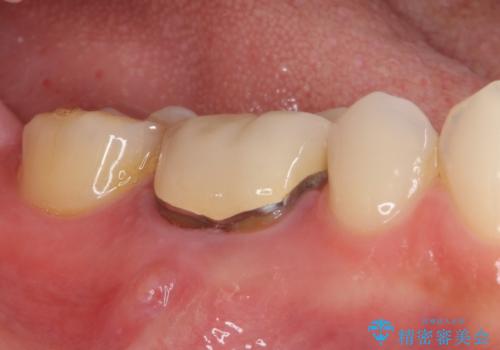

- 奥歯の歯肉から膿が出てくるとのことで来院された患者様です。

膿が出るようになるまでは、咬合時に鈍痛を感じていたとのことで、歯内の感染が原因と考えられました。

レントゲン写真より、根尖部に病変があったことから、根管治療を行い、症状消失後に補綴治療を行うこととしました。